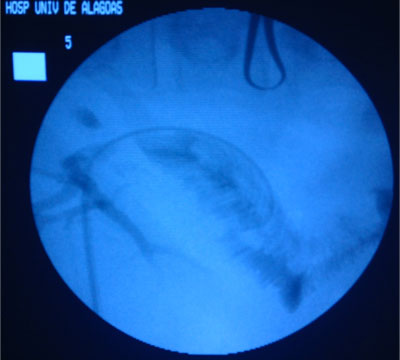

- Drenagem da Via Biliar e Dilatação da Estenose;

Dilatação com balão

- Balões maiores -> utilizados para a estenose do ducto biliar comum;

- Anastomoses biliares entéricas -> dilatação com um balão maior (10 a 20 mm de diâmetro);

Dilatação deve ser lenta e progressiva

- Evitar laceração do ducto biliar;

- Evitar sangramento no sistema biliar -> estenose fibrótica;